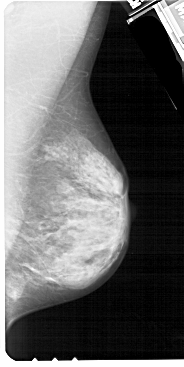

A_1338_1.RIGHT_CC

RIGHT_CC LINES 5041 PIXELS_PER_LINE 2626 BITS_PER_PIXEL 12 RESOLUTION 43.5 NON_OVERLAY